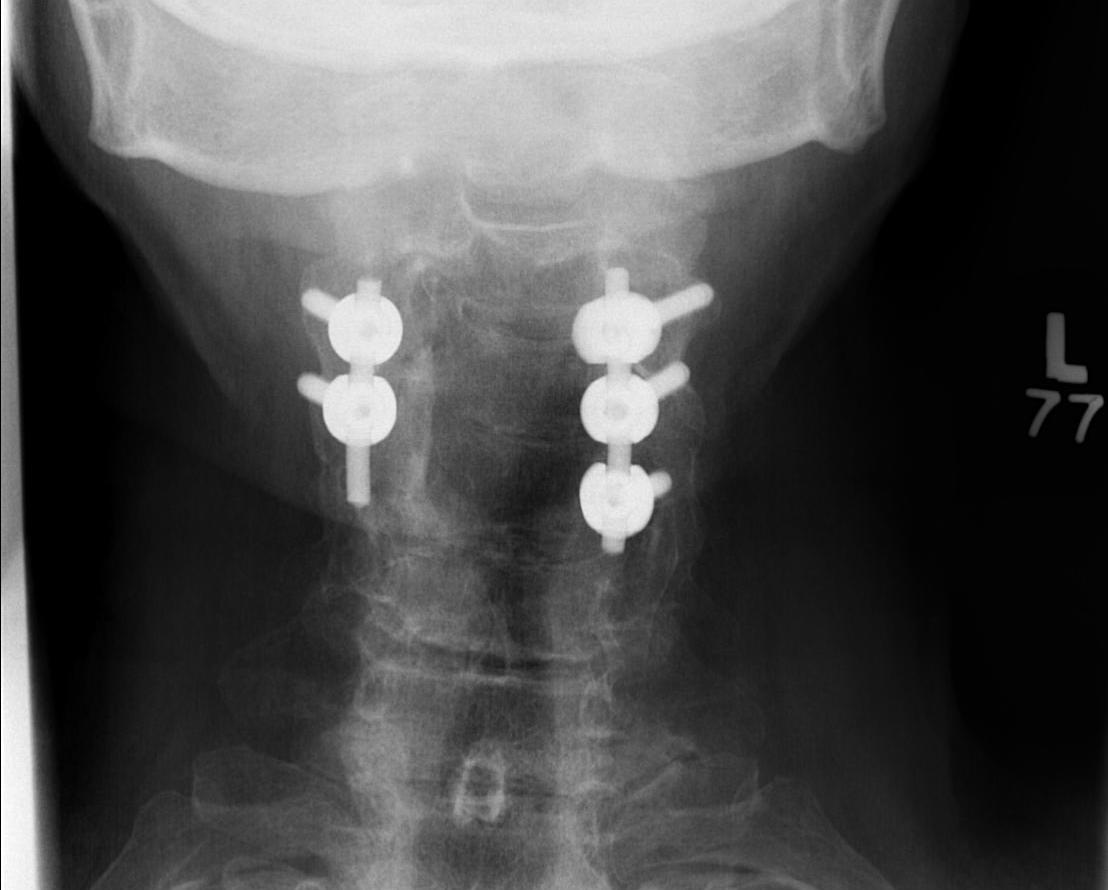

Posterior Instrumented Fusion

High complication rate

Leckie et al, Global Spine J 2016

- Database study of 1269 patients

- Adverse events 3 times more likely in posterior compared to anterior